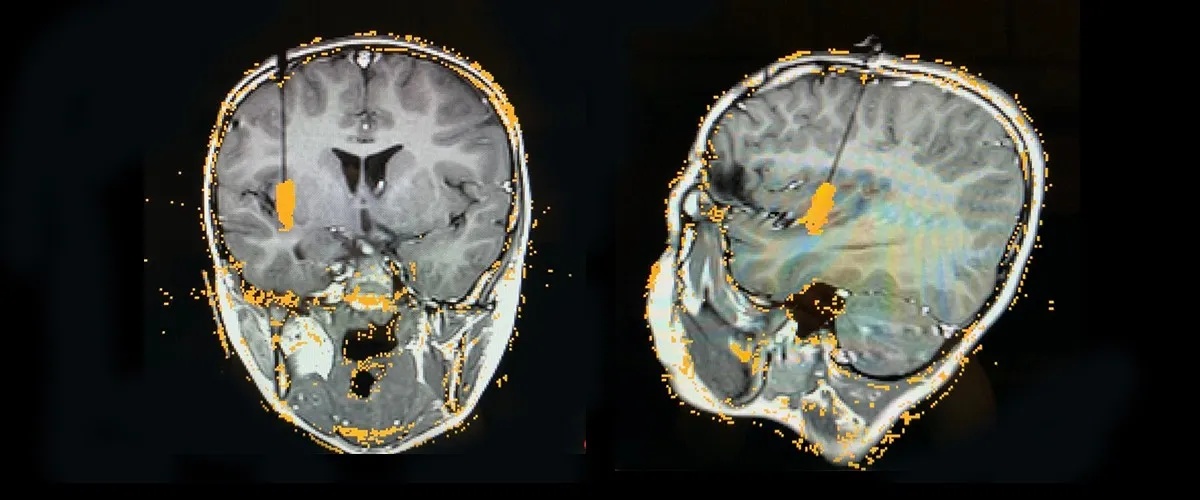

First stereo EEG: In 2019, Dr. Price performed a stereo EEG that revealed a tiny seizure focus in the insula, making the patient an ideal candidate for laser ablation.

Second stereo EEG: With the patient still having some seizures, Dr. Price and the epileptologists suspected the source was a complex network in the insula. She did another stereo EEG to confirm this hypothesis and identify other active regions.

Second laser ablation: In January 2021, he had his second laser ablation procedure that expanded the ablated lesion from the original treatment. He’s had very few seizures since.